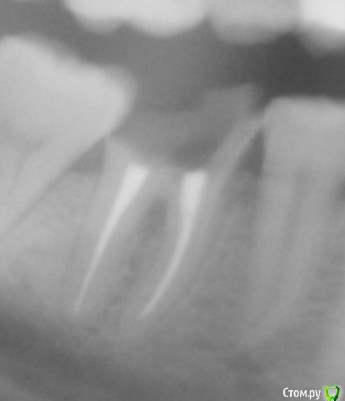

hysteresis Опубликовано 22 февраля, 2015 Поделиться Опубликовано 22 февраля, 2015 (изменено) Можно ли это восстановить, или удалять? Изменено 22 февраля, 2015 пользователем hysteresis Ссылка на комментарий

hysteresis Опубликовано 22 февраля, 2015 Автор Поделиться Опубликовано 22 февраля, 2015 Несколько лет. Как минимум с 2012-го года. Ссылка на комментарий

Гарриевич Опубликовано 22 февраля, 2015 Поделиться Опубликовано 22 февраля, 2015 Если он около трех лет в таком состоянии, то есть без пломбы и с открытыми устьями, то вряд ли. Но чтобы окончательно убедиться нужен очный осмотр Ссылка на комментарий

-SAE-Dantist_32 Опубликовано 23 февраля, 2015 Поделиться Опубликовано 23 февраля, 2015 здравия желаю парни,если зуб не подвижен,в чем я сомневаюсь то оно конечно попытаться можно лично сохранял еще и в худшем состоянии,но вы должны понимать такой зубик долго не прослужит 3-4 года максимум, Ссылка на комментарий